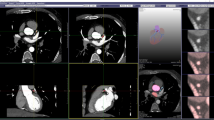

To enable high-quality physics-guided deep learning (PG-DL) reconstruction of large-scale 3D non-Cartesian coronary MRI by overcoming challenges of hardware limitations and limited training data availability.

While PG-DL has emerged as a powerful image reconstruction method, its application to large-scale 3D non-Cartesian MRI is hindered by hardware limitations and limited availability of training data. We combine several recent advances in deep learning and MRI reconstruction to tackle the former challenge, and we further propose a 2.5D reconstruction using 2D convolutional neural networks, which treat 3D volumes as batches of 2D images to train the network with a limited amount of training data. Both 3D and 2.5D variants of the PG-DL networks were compared to conventional methods for high-resolution 3D kooshball coronary MRI.

Proposed PG-DL reconstructions of 3D non-Cartesian coronary MRI with 3D and 2.5D processing outperformed all conventional methods both quantitatively and qualitatively in terms of image assessment by an experienced cardiologist. The 2.5D variant further improved vessel sharpness compared to 3D processing, and scored higher in terms of qualitative image quality.

PG-DL reconstruction of large-scale 3D non-Cartesian MRI without compromising image size or network complexity is achieved, and the proposed 2.5D processing enables high-quality reconstruction with limited training data.